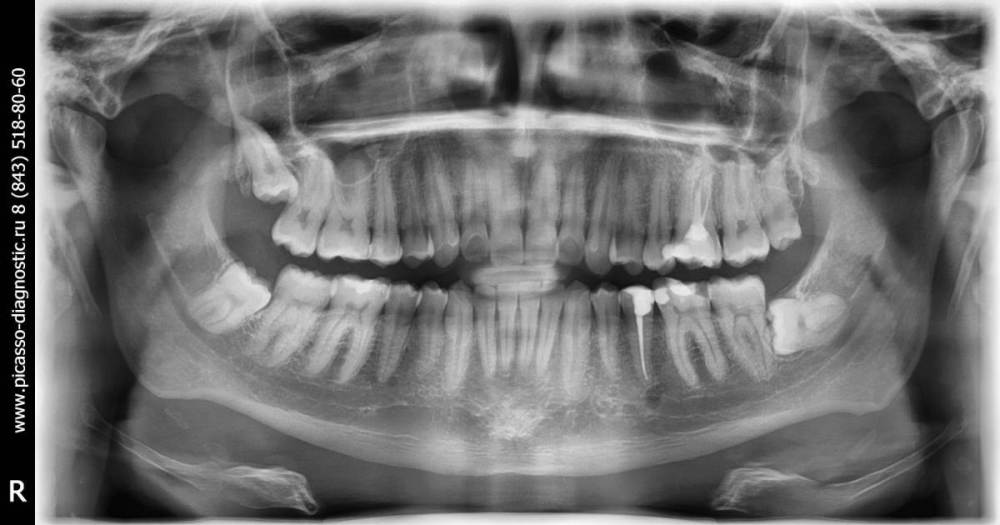

amkazan Опубликовано 5 мая, 2022 Поделиться Опубликовано 5 мая, 2022 Здравствуйте! ?Загорелся идеей ?! Возможна ли аутотрансплантация (пересадка) ретинированного (спрятанного в десне горизонтально) зуба на место 6ки. Донор: В последнее время начал чувствовать какую-то боль под зубами появляющуюся и исчезающую в челюсти слева ?, слегка докучающую, давил на зубы - они вроде не болят...и потом до меня дошло, что скорее всего это начал давить мой горизонтальный зуб мудрости. Как вы видите есть горизонтальный зуб ? слева (на снимке он справа снизу). И решил, что видимо пора удалять! И подумал: А что если его не просто удалить, а пересадить на место другого!? Замещаемый: 6ка сверху слева. Он из всех моих зубов по состоянию самый "уставший". Нерва там нет давно, потихоньку он темнеет и крошится что ли, и он начал чувствоваться. Не то чтобы очень не приятно, но как будто десна под ним устала. Такое ощущение. Не очень приятное, но не боль и можно игнорировать по идее.. но было бы здорово, чтобы этого чувства не было. И вот я думаю: Высоковероятно, что он кандидат номер 1 на удаление в будущем. Насколько далёком? Неизвестно. Конечно он может и всю жизнь простоять, но если есть новенький в запасе, то почему нет. (Плюс можно избежать сложного удаления в будущем, в случае если он начнёт крошиться при удалении и удалить его пока он ещё более менее крепкий?) Засим, прошу ответить Вас на 2 вопроса: 1) Стоит ли отказаться от этой идеи, так как 6ка ещё вполне хорошая? Или он уже реальный кандидат на удаление? 2) Вообще эта идея возможна ли? Резонна ли? Целесообразна ли? Спасибо!!! p.s. Снимок 2018 год, но в принципе там ничего не изменилось, только 8ку сверху удалил p.p.s. Так же 8 фотографий 6ки Ссылка на комментарий

Irouil Опубликовано 5 мая, 2022 Поделиться Опубликовано 5 мая, 2022 Сделайте свежие снимки, лучше всего КТ, если нет отрицательной динамики в области 6-ки - его под коронку, 8-ку удалить Аутотрансплантация этой (левой нижней) восьмёркой нерациональна, правые (нижней и верхней) можно пробовать трансплантировать, но тоже затруднительно, прогноз такой операции сомнительный 1 Ссылка на комментарий